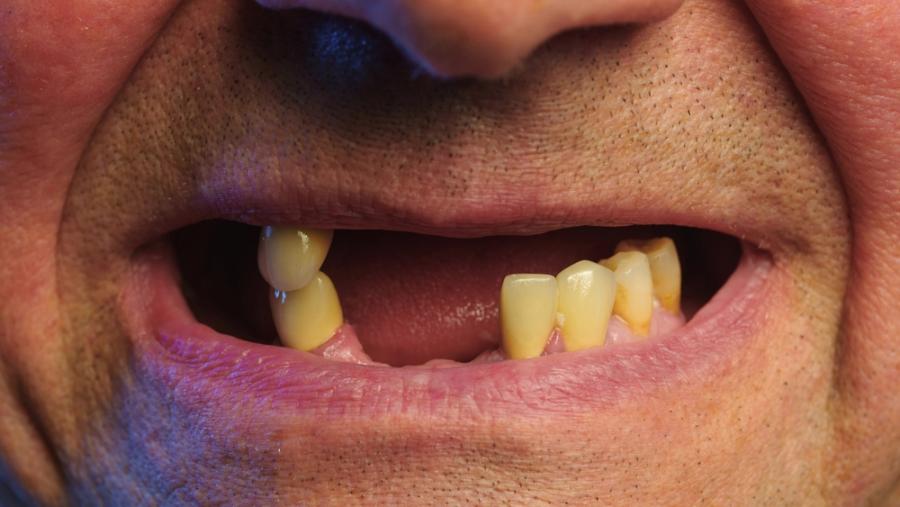

Теоретично това ново лечение, разработвано в Япония, би могло да позволи на хората да възстановят изгубените си зъби по същия начин, по който и на децата им израстват нови след падането на млечните. Изследователите описват новия процес като начало на "трето поколение" на регенерация на зъбите, като първото е появата на млечните при бебетата, а второто - постоянните зъби на възрастните, които се появяват по-късно в детството.

Предположението, че лекарствената терапия може да бъде достъпна за широка употреба още в началото на следващото десетилетие, звучи доста оптимистично, но е очевидно, че екипът вярва, че е постигнал нещо значимо.